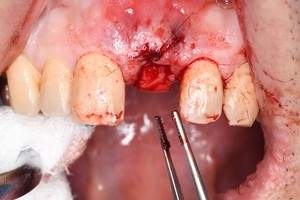

症例写真-2

- Befor

- 途中経過

- After

| 年齢 | 50代・男性 |

| 主訴 | 右下歯が疼く |

| 治療内容 | ・右下6番インプラント ※1:FGG(遊離歯肉移植術)とは、足りない歯ぐきを上顎から上皮を切り取り移植する外科手術 |

| 治療費 | 合計:902,000円(税込) ■内訳 |

| 治療期間 | 9ヵ月 |

| 治療方針 | 右下の当該歯は歯根破折により保存不可能と診断しました。歯周疾患も伴っていたため抜歯後に骨吸収※1が大きく起こることが予測できました。チタンメッシュ併用骨再生誘導法(GBR※2)を選択しインプラント埋入と同時に行い自然な歯槽骨のラインを再現しました。またGBRを行う際にインプラント辺縁の付着歯肉の減少が起こる為、遊離歯肉移植術(FGG※3)を行い清掃性を考慮した形態に仕上げました。 ■治療方針の解説 治療した右下の歯をレントゲンで撮影したところ根本の部分に黒く写る箇所があり「根尖性慢性周囲炎※1」と診断。また歯周病も進行していました。 ※1 骨吸収・・・歯槽骨という歯を支える骨がなくなっていくこと |

| 担当者所見 | 主訴の右下だけでなく歯茎の腫れ、発赤があり不良補綴や不良充填など他にも治療箇所が多数ありました。プラークコントロールが不良であった為まずはブラッシング指導を行いセルフケアの重要性を理解していただくところからスタートしました。 右下6番の歯はインプラント治療を行なった結果審美的にも機能的にも患者様の満足を得ることができました。骨造成と歯肉移植も行なった為インプラントを支える十分な歯周組織の獲得ができたと思っております。 |